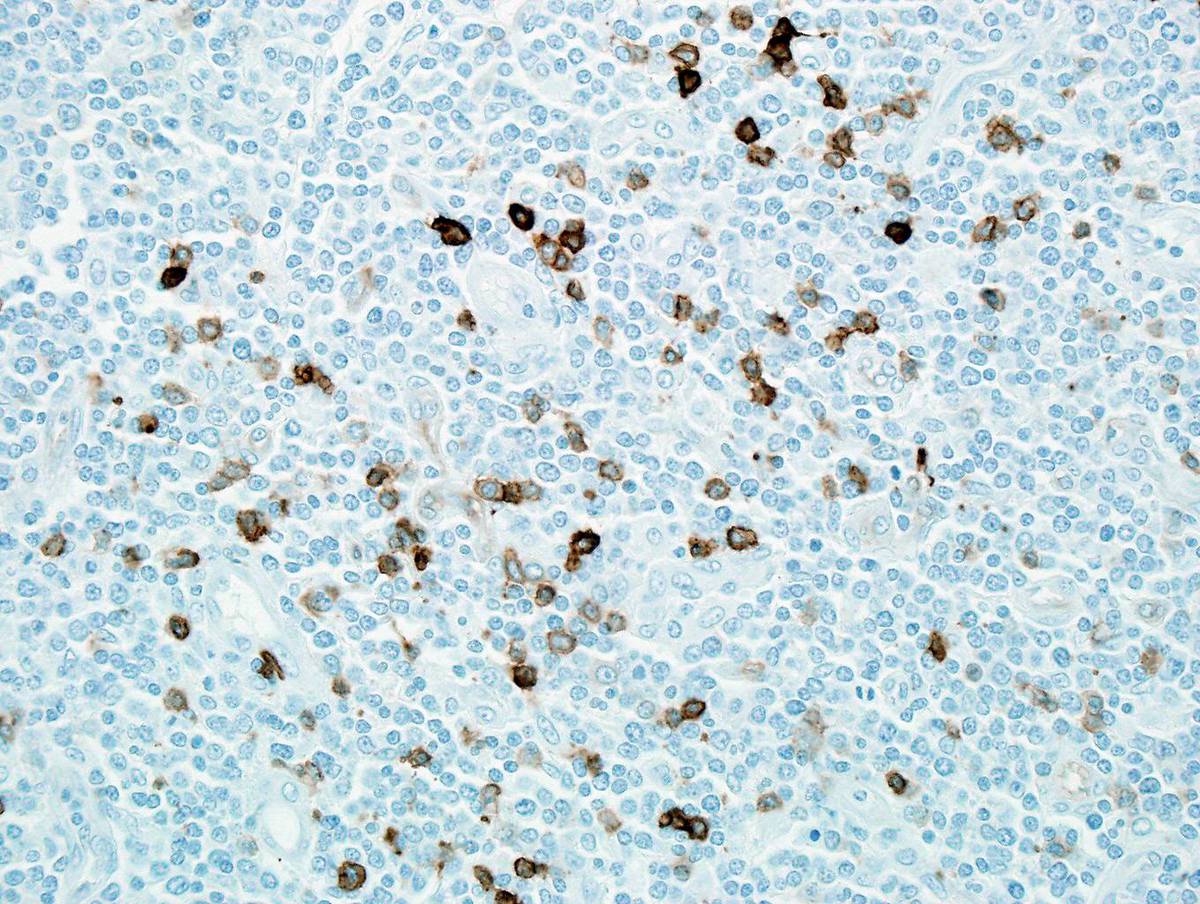

Immunohistochemistry: Blastic cells were positive for CD1a, CD2, CD3, CD4, CD5, CD7, TdT, and Ki67 (almost 100% labeling index). Blastic cells were negative for B-cell markers. A few cells were positive for CD117, CD15, CD33, myeloperoxidase, and lysozyme.Flow cytometric analysis: Blast cells were positive for CD45 (intermediate intensity), CD1a, CD2, cytoplasmic CD3, CD4, CD5, CD7, CD56 (dim), CD99, and TdT. There was loss of surface CD3. B-cell markers were negative. Myeloid markers were not used in the panel.B. First Bone Marrow:Immunohistochemistry: Rare CD34+ blasts, a few myeloperoxidase+ cells, a few small CD20+ cells, a few small CD3+ cells, no TdT+ cells, and many CD61+/Fctor VIII-related antigen+ megakaryocytes.C. Second Bone Marrow:Immunohistochemistry: Numerous CD34+ blasts, no CD3+ blasts, a few CD117+/myeloperoxidase+ cells, no TdT+ cells.Flow Cytometric Analysis: Myeloblasts accounted for approximately 80% of all cells analyzed and demonstrated posivity for: CD45, CD34, CD33, CD13, HLA-DR, CD11b,myeloperoxidase, CD15, CD4, CD5 (dim), CD7 (dim), and My4 (dim). Blasts did not express CD1a, CD2, CD3, CD8, CD19, CD20, CD10, CD56, CD117, CD16, CD64, Mo2, or TdT.CYTOGENETIC FINDINGS

| Immunostain for CD33 shows a few positive cells. | ![]() |

| Immunostain for myeloperoxidase shows a few positive cells. | ![]() |